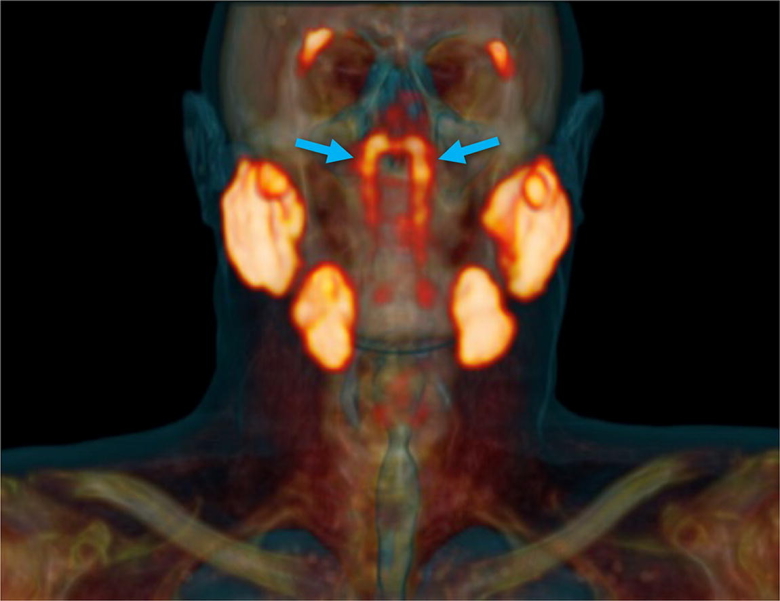

Голландские ученые обнаружили неизвестный прежде науке орган в голове человека

Как это открытие повлияет на лечение рака?

Голландские ученые обнаружили скрытый внутри головы человека орган, напоминающий набор слюнных желез, неизвестный ранее науке. Открытие было сделано случайно: в ходе контрастной томографии с введением в кровь онкологических больных радиоактивной глюкозы.

При обследовании сотни пациентов с раком простаты с помощью нового сканера PSMA PET/CT радиологи и онкологи обнаружили нечто странное. У людей три пары больших слюнных желез – околоушные, подчелюстные, подъязычные. «Но не в этом месте, – объясняет открытие радиолог-онколог Воутер Фогель из Нидерландского института рака. – Слюнные железы в носоглотке микроскопически малы: около тысячи их равномерно распределены по слизистой оболочке. Поэтому представьте себе наше удивление, когда мы увидели на снимках эти железы».